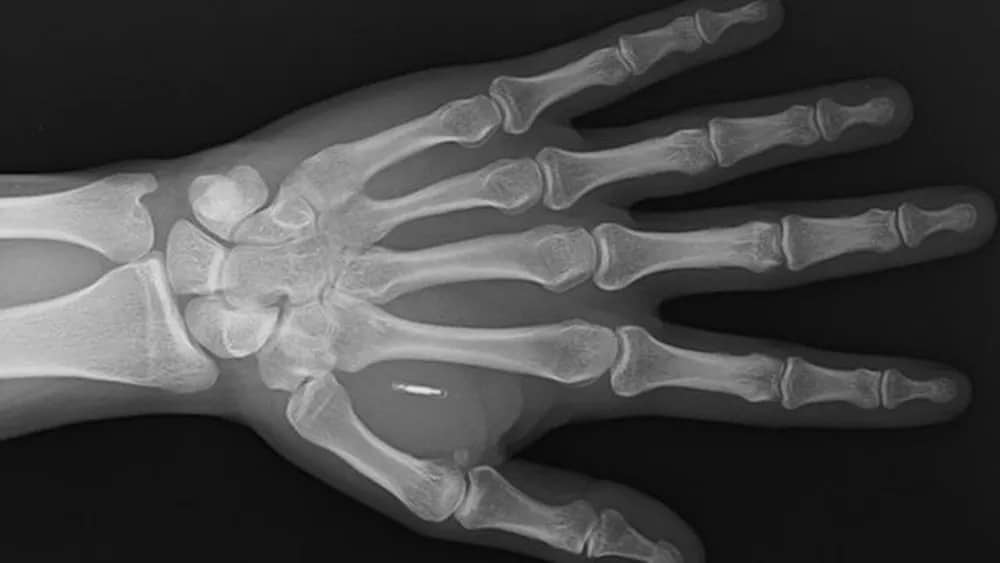

O chip é mais ou menos do tamanho de um grão de arroz e pesa menos de uma grama. Ele é inserido sob a pele e é feito de biopolímetro, um material semelhante ao plástico, que envolve uma antena e um microchip.

A tecnologia utilizada nos chips é a NFC, mesmo sistema de pagamento por aproximação utilizado nos smartphones, ela também é conhecida por comunicação de campo próximo aqui no Brasil.